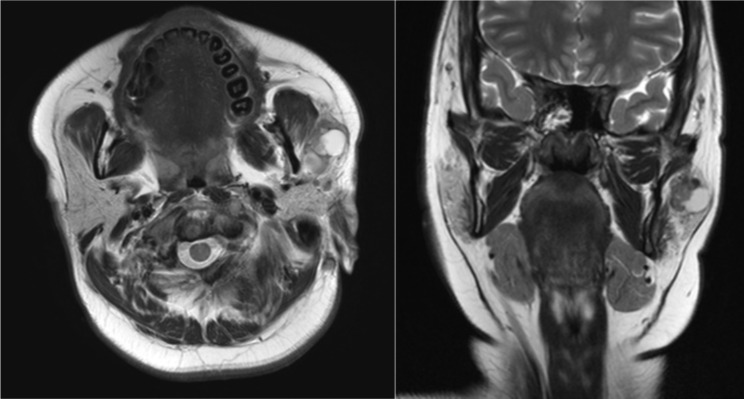

Backgrounds: Preoperative imaging, particularly with magnetic resonance imaging (MRI) and computed tomography (CT) scans, plays a crucial role in distinguishing between benign and malignant parotid gland tumors, while the reliability of Ultrasound-Guided Fine Needle Aspiration (FNA) in diagnosing these masses remains a topic of debate.

Methods: This two-center retrospective analysis was conducted on 347 patients with parotid gland tumors who had FNA and preoperative imaging (CT or MRI). All patients underwent surgery and final histopathological examination was available, along with complete medical records between January 2008 and May 2023.

Results: Among the 347 patients, 318 (92%) had benign and 10 (3%) had malignant tumors based on FNA, with 19 (5%) unsatisfactory specimens. Final histological diagnosis revealed 303 (87%) benign and 44 (13%) malignant lesions, with a false-negative rate of 10.6% for FNA. Multivariate analysis identified irregular shape and invasion as independent predictors of malignancy in patient with benign or unsatisfactory FNA results. The odds ratio for irregular shape was 3.06 and for invasion was 12.73.

Conclusion: Imaging characteristics, such as irregular shape and invasion may indicate towards malignant parotid tumors, even in patients with false-negative benign findings in FNA.